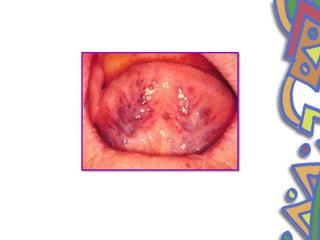

• Oral varicosities

• Varicosities are aquired benign lesion of a vein, artery or lymphatic

vessel abnormally dilated and tortuous but in within oral cavity is

only used in reference to venous lesions

• sublingual varix

• Males

• over 50years

• Clinical features

• Irregular, blue purple lesion

• Multiple with a bilateral linear distribution

• Thrombosed varix

• Diascopy